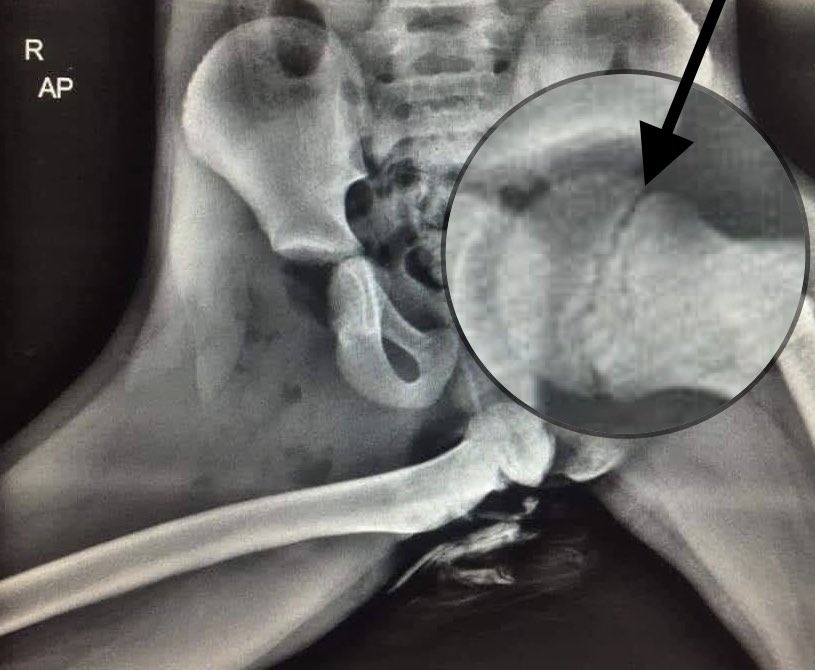

Mais celle d& #39;un enfant... comme on peut le voir ici (fléchés) car les cartilages de croissance des fémurs ne sont pas soudés (le trait noir entre l& #39;epiphyse et la métaphyse) contrairement à une hanche adulte.

(Il y a d& #39;autres signes en faveur d& #39;un enfant)

(Il y a d& #39;autres signes en faveur d& #39;un enfant)